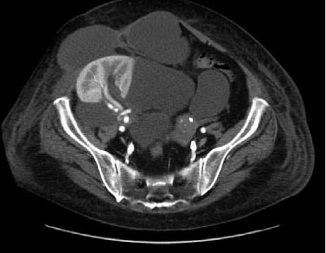

En el trasplante renal heterotópico ¿cómo se realizan las anastomosis?

Answer

• Arteria renal a ilíaca externa en termino-lateral, y vena renal a vena ilíaca externa en termino-lateral.

• Arteria renal a ilíaca externa en termino-terminal, y vena renal a vena ilíaca externa en termino-lateral.

• Arteria renal a ilíaca interna en termino-lateral, y vena renal a vena ilíaca externa en latero-lateral.

• Arteria renal a ilíaca interna en termino-lateral, y vena renal a vena ilíaca interna en termino-lateral.